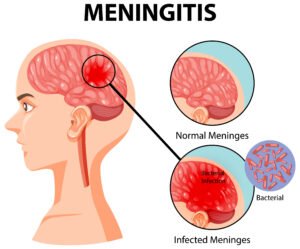

- Brain Fever

- Meningitis